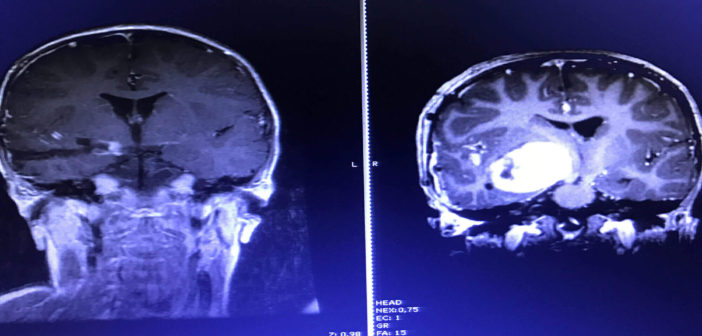

“El desarrollo de las neuroimágenes nos permite comprender aún más el cerebro. No sólo en relación a su anatomía, sino que también en sus funciones y conexiones, a modo de disminuir las eventuales secuelas que podemos dejar en nuestros pacientes”, afirma el neurocirujano, quien hace énfasis en las nuevas técnicas de resonancia que permiten ver pequeñas lesiones o malformaciones estructurales, o bien alteraciones metabólicas a nivel cerebral que ayudan al estudio de, por ejemplo, pacientes con epilepsia refractaria. “El último cambio importante ha sido en la reciente década y ha generado importantes diferencias, logrando incluso curar a pacientes que de no haber sido operados, aún persistirían con crisis con el consiguiente aumento de su morbimortalidad”, explica el especialista.

Una de las principales preocupaciones del especialista son los tumores del sistema nervioso central, “Hoy en día los tumores del sistema nervioso central son la principal causa de muerte por cáncer a nivel infantil en el mundo. Si bien hoy en día conocemos de mejor manera la genética de los tumores, no se ha logrado llegar a grandes avances en el tratamiento coadyuvante de nuestros pacientes, como sí se ha logrado en otros tipos de cánceres infantiles, como por ejemplo las leucemias”, insiste el Dr. Vigueras.